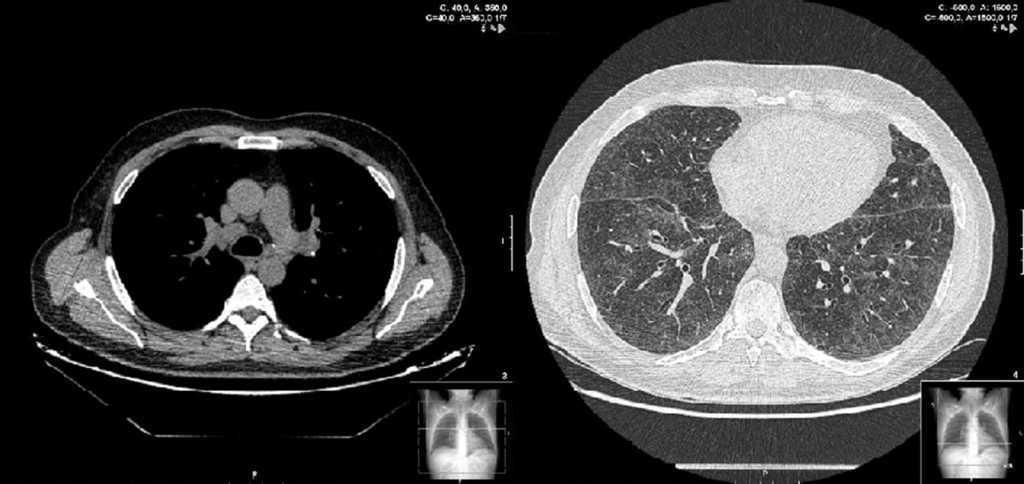

Two weeks later, the patient presented clinical improvement (after drug treatment with antibiotics and bronchodilators) but with persistent injury in chest radiography, so a thoracic CT was performed, showing bilateral and diffuse ground-glass opacities, multiple centrilobular micronodules (Figure 1) and mediastinal lymphadenopathy. Bronchoscopy was normal, and transbronchial biopsy showed the presence of non-necrotizing granulomas. Ziehl Neelsen, and Groccott staining were negative, as PCR and mycobacteria culture. After completing HCV treatment, the clinical course of the patient was favorable, showing the following thoracic CT gradual improvement in lung and lymph node involvement, and finally, a year later, the resolution of the disease (Figure 2).

Figure 2. Sarcoidosis in 50 years-old man, coinfected with HIV and HCV, and treated with telaprevir-based triple therapy. Thin-section of thoracic CT shows sarcoidosis resolved a year after stopping HCV treatment. Small calcified micronodules are observed.